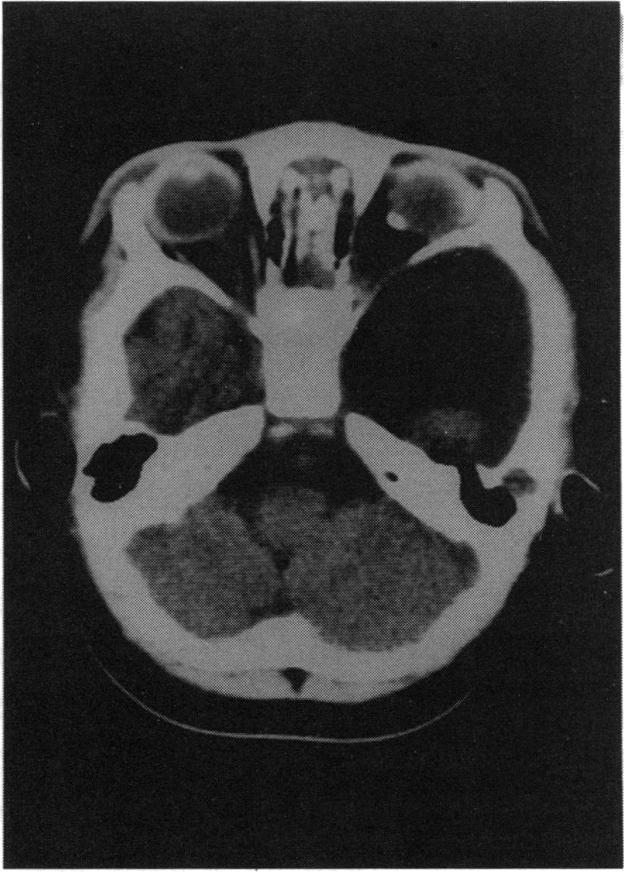

We identified five patients with the organoid nevus syndrome. Four had a classic sebaceous nevus in the facial and scalp area, and 2 had seizures and arachnoid cysts. All 5 patients had an epibulbar tumor, which proved to be a complex choristoma in one case that was studied histopathologically. A characteristic ophthalmoscopic feature, observed in the 4 patients with clear ocular media, was a flat yellow discoloration of the posterior fundus, of variable size and shape, which appeared to correlate with a dense plaque noted on ultrasonography and computed tomography. In 1 case, histopathologic examination showed that this posterior lesion contained intrascleral cartilage.

我们确定了5例器官样痣综合征患者。4例在面部和头皮区域有典型的皮脂腺痣,2例有癫痫发作和蛛网膜囊肿。所有5例患者均有眼球表面肿瘤,其中1例经组织病理学研究证实为复合性脉络膜瘤。在4例眼介质清晰的患者中观察到一个特征性的眼底镜特征,即眼底后部有扁平的黄色变色,大小和形状各异,这似乎与超声检查和计算机断层扫描中发现的致密斑块相关。在1例中,组织病理学检查显示该后部病变含有巩膜内软骨。